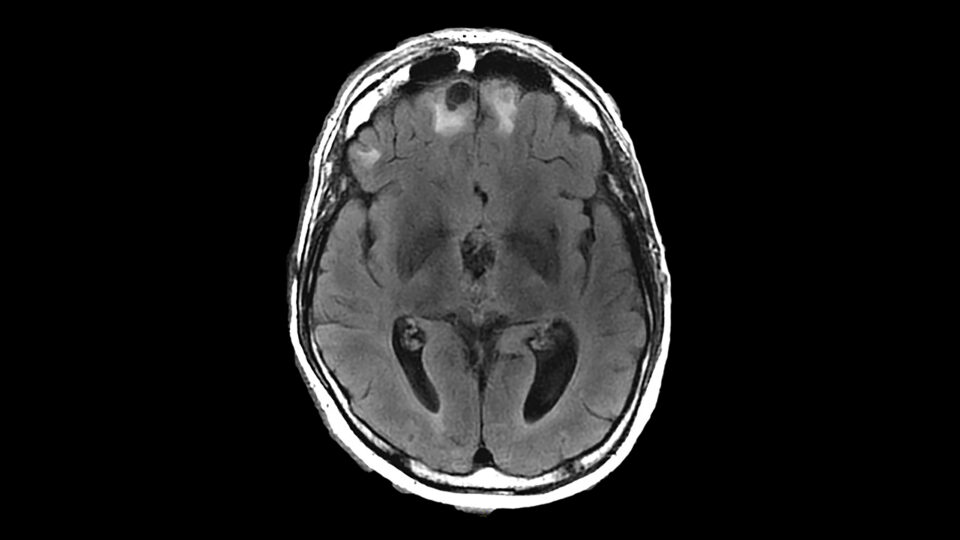

One use of tDCS is to direct the current to the region of the brain that is engaged in a training activity. A growing body of evidence shows that this method, known as “functional targeting,” can boost and harness the outcomes of other therapies. Imaging studies suggest it works by increasing cerebral blood flow in key areas and strengthening neuroplasticity.